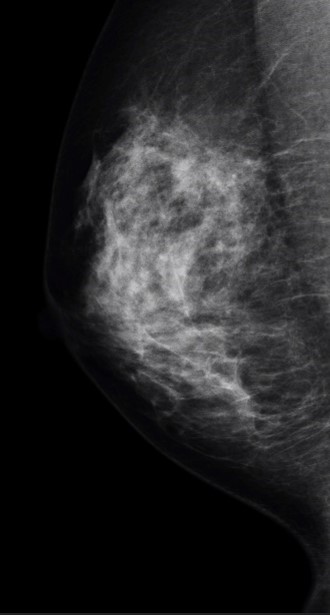

乳房撮影検査(マンモグラフィ)とは乳房の単純X線撮影です。

乳房全体を写し出すために、乳房を薄く伸展し、板で圧迫と固定を行い、撮影します。

乳房撮影では小さな石灰化像を写すことができ、早期乳がんの診断に有効な検査です。

乳房2方向撮影

左右の乳房に対し、2方向(MLO:内外斜位方向とCC:頭尾方向)合計4枚撮影します。 また、さらに詳しく精査を行うために、追加撮影をお願いすることもあります。